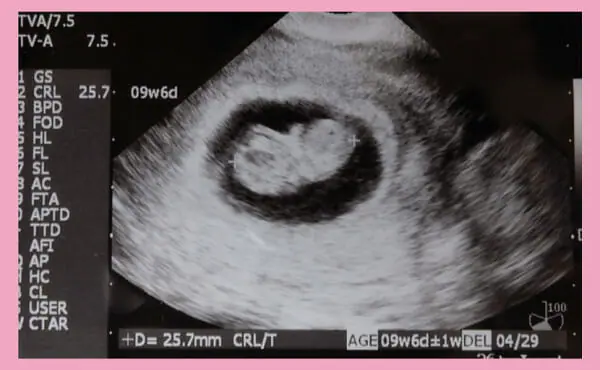

Baby at 9 weeks’ gestation

At 9 weeks’ gestation, the baby’s size (foetal cephalic length: CRL) is 20-30 mm, the gestational sac (GS) is 5.7 cm and the weight is around 1-3 g. It is just the size of a strawberry. The foetus is developing into a human-like shape, with a separation and a head and body. This is also the time when the face, fingers and toes and other small parts of the body are gradually being formed. The reproductive organs will also begin to develop around 9 weeks’ gestation.

The foetal heartbeat is also at its fastest at 9 weeks’ gestation. The foetal heart rate is around 90-100 beats per minute at 5 weeks’ gestation, which is often the first time it is confirmed by ultrasound at this time. The heart rate increases steadily until the ninth week of pregnancy, peaking at 170-180 beats/minute in the middle of the ninth week. Thereafter, the foetal heart rate gradually decreases as the gestational weeks progress, stabilising at around 150 beats/min around 16 weeks’ gestation until the day of delivery.

Echocardiogram at 9 weeks’ gestation

Twice before 23 weeks’ gestation. If the date of ovulation cannot be determined, the cephalic length (CRL) at 8-10 weeks’ gestation is measured by echocardiography and used to estimate the expected date of delivery. The test is also considered a prenatal diagnosis in the broadest sense, as it provides a direct view of the baby in the abdomen.

A mother’s biggest concern during pregnancy is the health of her baby. At around 9 weeks’ gestation, the baby’s heartbeat can be clearly seen by ultrasound. However, the baby is still very small at this time and an echo scan cannot detect conditions such as 21 trisomy (Down syndrome).